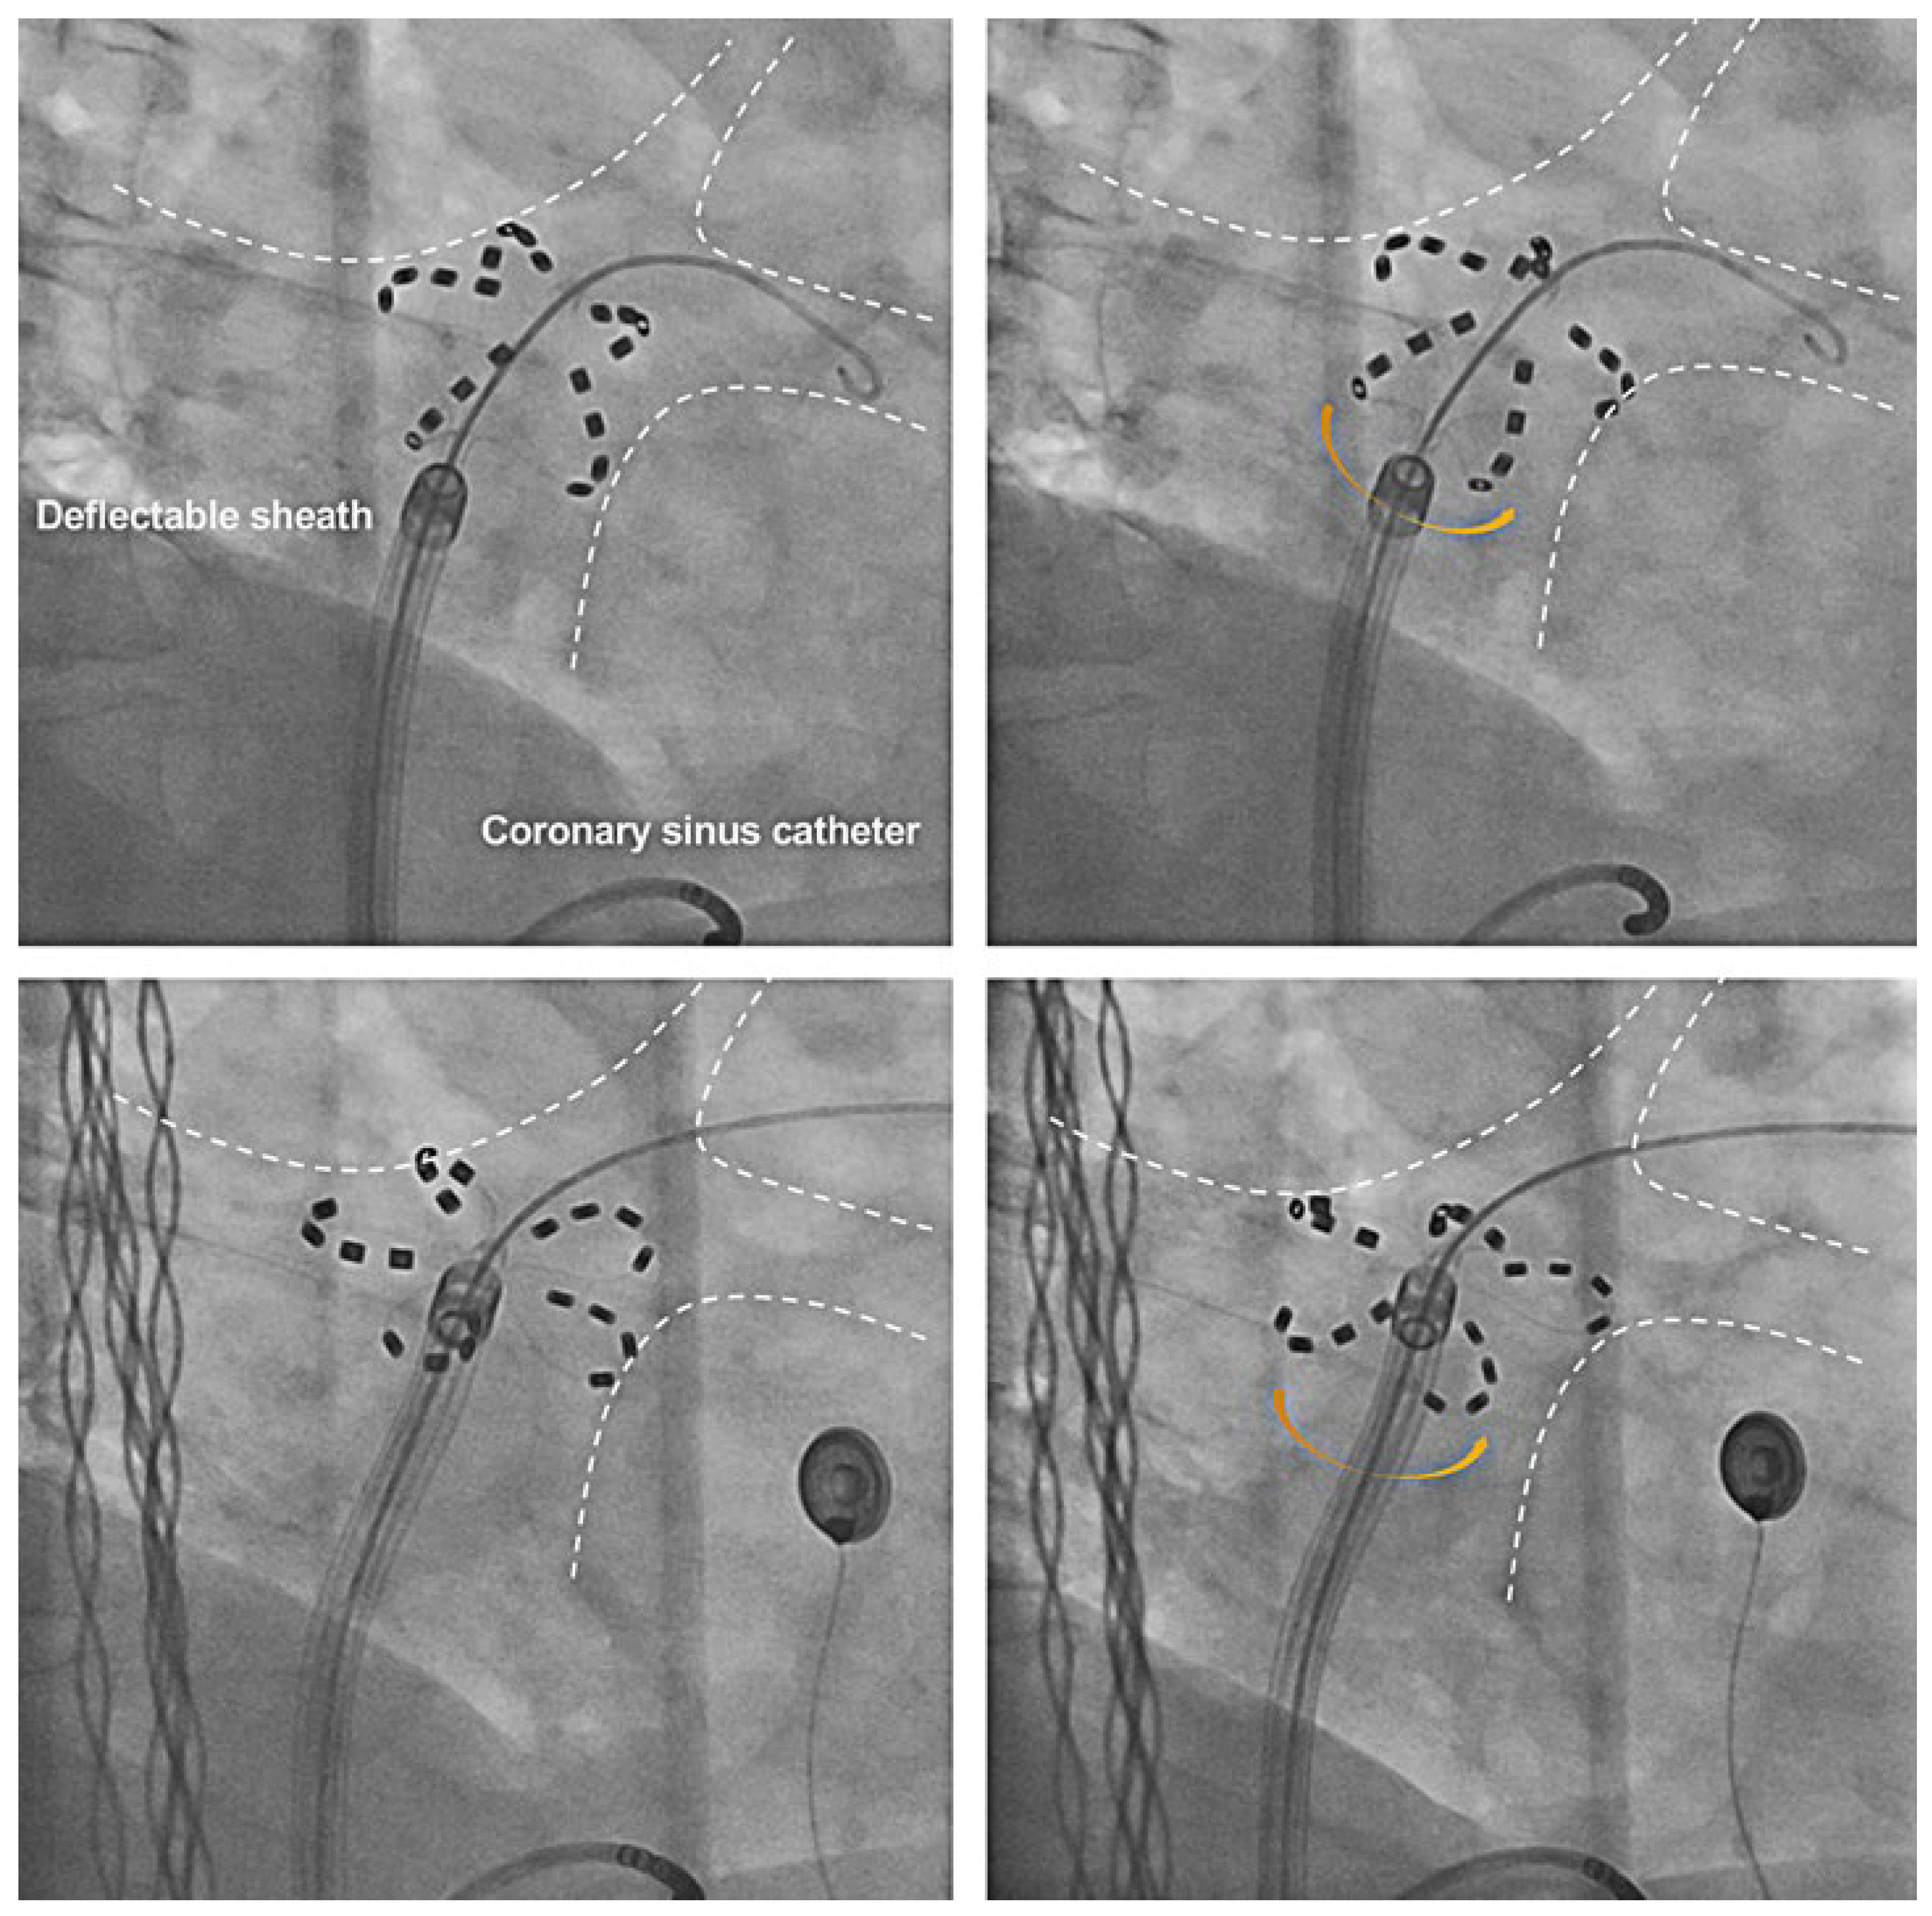

Workflow of a PFA Procedure Using the FARAPULSE™ System

- Kueffer, T.; Madaffari, A.; Thalmann, G.; Mühl, A.; Galuszka, O.; Baldinger, S.; et al. Eliminating transseptal sheath exchange for pulsed field ablation procedures using a direct over-the-needle transseptal access with the Faradrive sheath. Europace 2023, 25, 1500–1502. [Google Scholar] [CrossRef]

- Schmidt, B.; Bordignon, S.; Tohoku, S.; Chen, S.; Bologna, F.; Urbanek, L.; et al. 5S Study: Safe and Simple Single Shot Pulmonary Vein Isolation With Pulsed Field Ablation Using Sedation. Circ Arrhythm Electrophysiol. 2022, 15, e010817. [Google Scholar] [CrossRef] [PubMed]

- Kueffer, T.; Baldinger, S.H.; Servatius, H.; Madaffari, A.; Seiler, J.; Mühl, A.; et al. Validation of a multipolar pulsed-field ablation catheter for endpoint assessment in pulmonary vein isolation procedures. Europace 2022, 24, 1248–1255. [Google Scholar] [CrossRef] [PubMed]